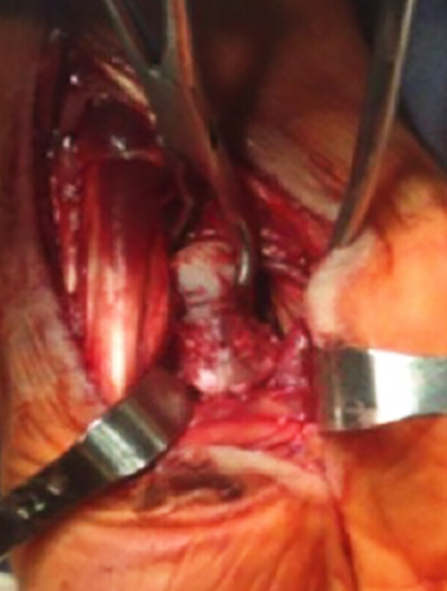

Paciente de sexo masculino, de 26 años, diestro, sin antecedentes personales a destacar, que fue embestido por automóvil mientras manejaba su moto. El paciente presentó una lesión encefálica focal que requirió tratamiento médico. Estuvo en coma 20 días, aparentemente sin otras lesiones. Luego, ya con vida de relación retomada, el paciente relató dolor e impotencia funcional de su mano derecha. Tumefacción y dolor a la movilización (pasiva-activa) y a la prehensión en el examen físico. Las radiografías y el TC mostraron una luxación volar de hueso grande de mano derecha (Figura 1) asociada a fracturas de la base del tercer metacarpiano y de hueso piramidal, ambas sin desplazamiento (Figura 2). A las 8 horas de establecer el diagnóstico se realizó una reducción abierta por vía palmar con fijación interna, con alambres de Kirchner de 1,5 mm, (Figura 3). Se agregó un mini fijador externo para proteger la estabilidad de la osteosíntesis del carpo y manejar las partes blandas lesionadas. No se realizó reconstrucción ligamentaria.

Lee et al (2) y Lorwey et al (5) mostraron en sus trabajos lesiones asociadas a la luxación del hueso grande. Comparando nuestro caso con los anteriores, coincidimos en que el mecanismo de esta lesión es por hiperextensión y carga axial con la mano pronada. Además, con un movimiento de desviación radial en el momento de la carga que concluye con las fracturas observadas en los demás huesos del carpo. A pesar de la rotura de los ligamentos radio-escafo-capitato, capito-triquetral, interoseos y piramido-ganchoso-capitato no actuamos sobre la parte ligamentaria porque el grave compromiso ligamentario del propio traumatismo, asociado al tiempo de evolución, dificultó el reconocimiento de las estructuras anatómicas.